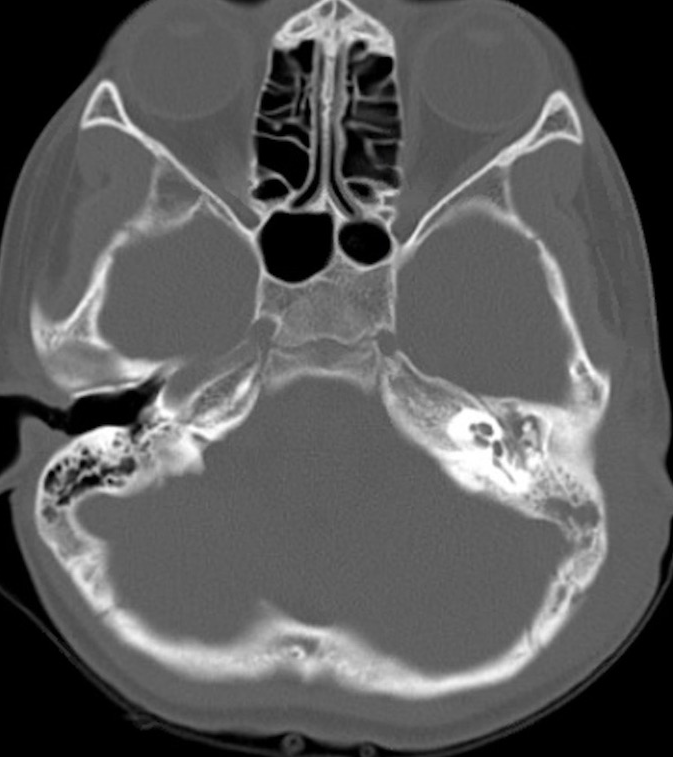

The patient had bloodwork completed, which was significant for leukocytosis to 15.5 (ref range: 4.5–13.5 103/μL) with a left shift and elevated CRP to 32.8 (ref range: 0.0 - 8.2 mg/L). CBC also demonstrated a normocytic anemia with Hgb 9.3 (ref range: 11.5 – 15.5 g/dL), and CMP was notable for mild hypoalbuminemia of 2.6 (ref range: 3.2 – 4.7 g/dL), but labs were otherwise unremarkable. He was started on empiric IV Ampicillin-Sulbactam (Unasyn). While awaiting transfer to a pediatric facility, the patient underwent a CT temporal bone with/without contrast, which revealed the following (Figure 3).